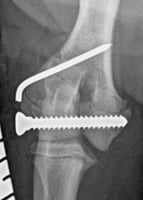

Managing humeral intracondylar fissure

Humeral intracondylar fissure (HIF) is a condition that is most often seen in Spaniel breeds, partic...

8 min read